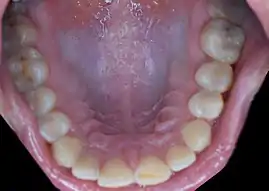

Rugae folds behind the anterior teeth in the hard palate of the mouth

In anatomy, rugae (sg.: ruga) are a series of ridges produced by folding of the wall of an organ.[1] Most commonly rugae refers to the gastric rugae of the internal surface of the stomach.

Rugae can appear in the following locations in humans:

With few exceptions (e.g. the scrotum), rugae are only evident when an organ or tissue is deflated or relaxed. For example, rugae are evident within the stomach when it is deflated. However, when the stomach distends, the rugae unfold to allow for the increase in volume. On the other hand, plicae remain folded regardless of distension as is evident within the plicae of the small intestine walls.